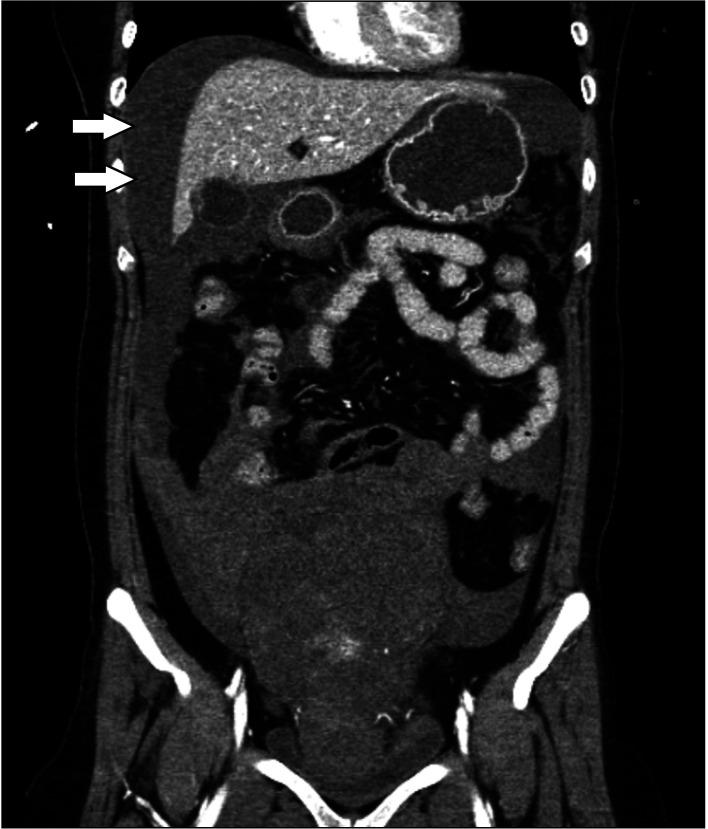

Uterine fibroid, or leiomyoma, is a common benign neoplasm in women, but serious complications are rarely reported. We present the case of a 48-year-old woman with acute onset of abdominal pain. She was hemodynamically unstable, and computed tomography revealed abundant fluid collection in the peritoneal cavity, suggesting hemoperitoneum. During emergency exploratory laparotomy, the subserosal vein overlying a uterine fibroid was identified as the source of bleeding. Hemostasis was accomplished with fibroid excision. Spontaneous hemorrhage originating from a uterine fibroid is extremely rare, but may lead to life-threatening conditions. Therefore, in female patients with acute abdominal pain and hemoperitoneum, uterine fibroid may be a potential etiology and emergency exploratory laparotomy should be considered.

摘要

子宫肌瘤,又称平滑肌瘤,是女性常见的良性肿瘤,但严重并发症鲜有报道。我们报告一例48岁急性腹痛女性病例。她血流动力学不稳定,计算机断层扫描显示腹腔内有大量积液,提示腹腔积血。在急诊剖腹探查术中,发现子宫肌瘤表面的浆膜下静脉是出血来源。通过切除肌瘤实现了止血。子宫肌瘤自发出血极为罕见,但可能导致危及生命的情况。因此,对于急性腹痛和腹腔积血的女性患者,子宫肌瘤可能是潜在病因,应考虑急诊剖腹探查术。